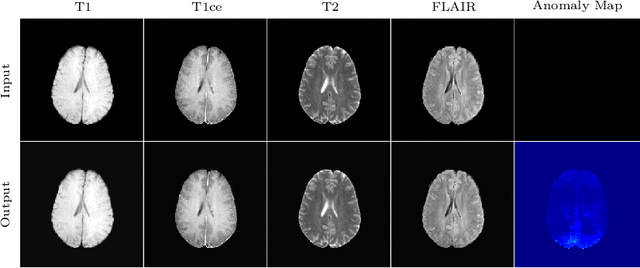

Abstract:In medical applications, weakly supervised anomaly detection methods are of great interest, as only image-level annotations are required for training. Current anomaly detection methods mainly rely on generative adversarial networks or autoencoder models. Those models are often complicated to train or have difficulties to preserve fine details in the image. We present a novel weakly supervised anomaly detection method based on denoising diffusion implicit models. We combine the deterministic iterative noising and denoising scheme with classifier guidance for image-to-image translation between diseased and healthy subjects. Our method generates very detailed anomaly maps without the need for a complex training procedure. We evaluate our method on the BRATS2020 dataset for brain tumor detection and the CheXpert dataset for detecting pleural effusions.